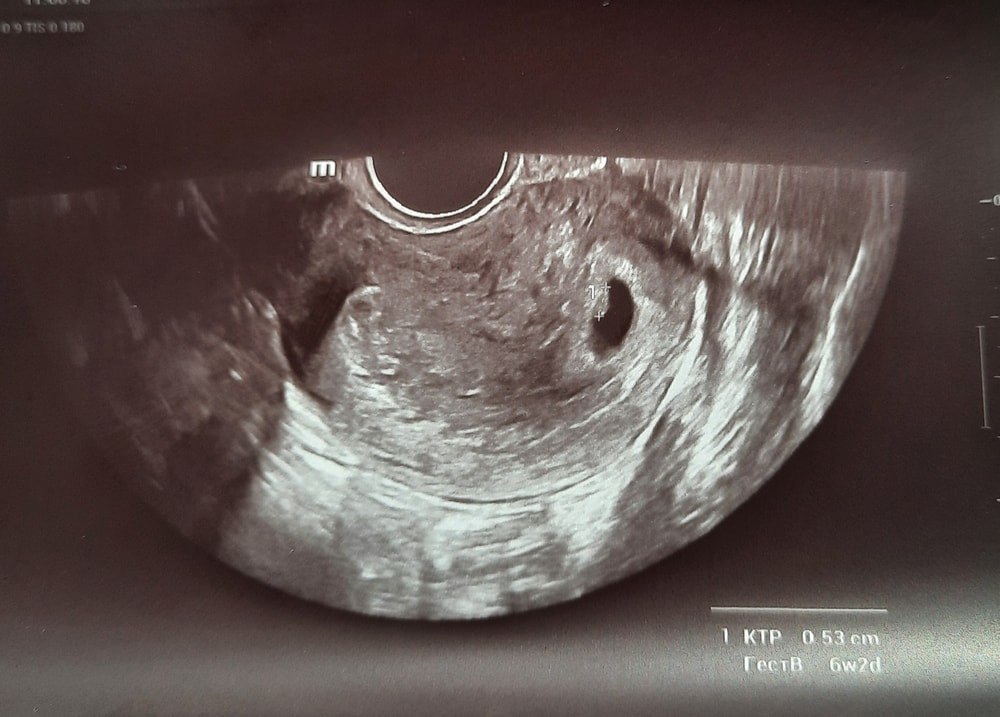

Маленькая фасолинка 😊

Раздвоение Птичности, да)) Узистка сказала, козюлечка такая😅